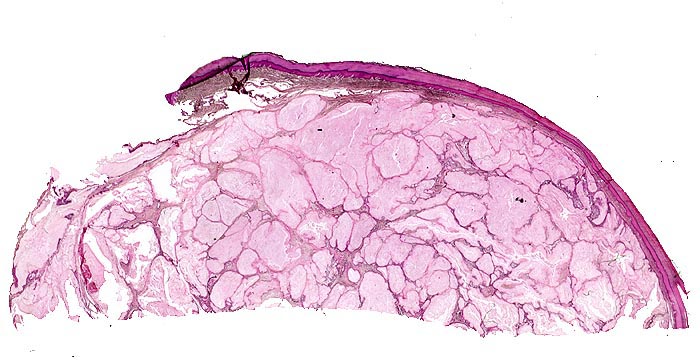

• Kollagenes Bindegewebe mit Tophus bestehend aus wolkiger eosinophiler Matrix mit herdförmig erkennbaren nadelförmigen Strukturen (Uratkristalle).

• Die Ablagerungen sind umgeben von mehrkernigen Fremdkörperriesenzellen, Makrophagen und wenigen neutrophilen Granulozyten.